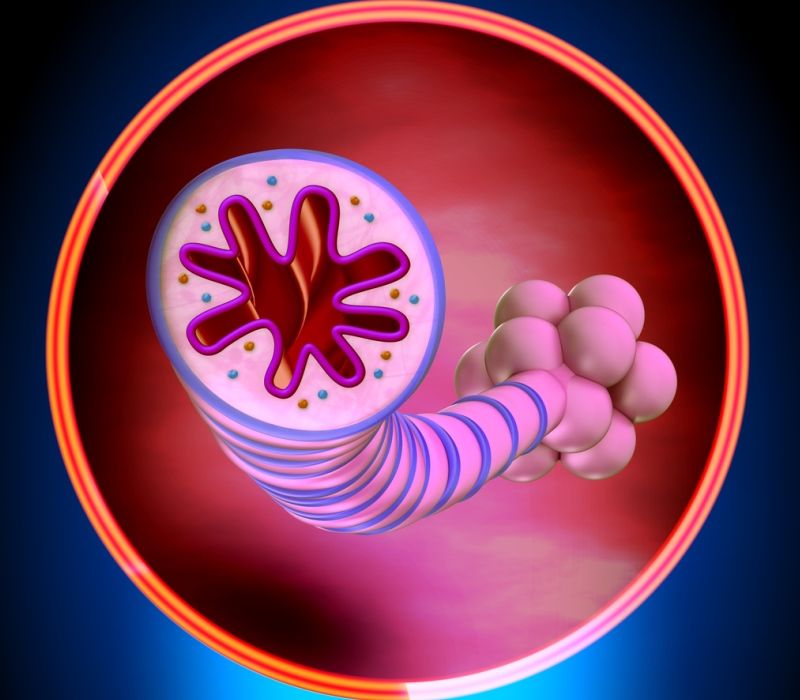

Neumología

Neumología